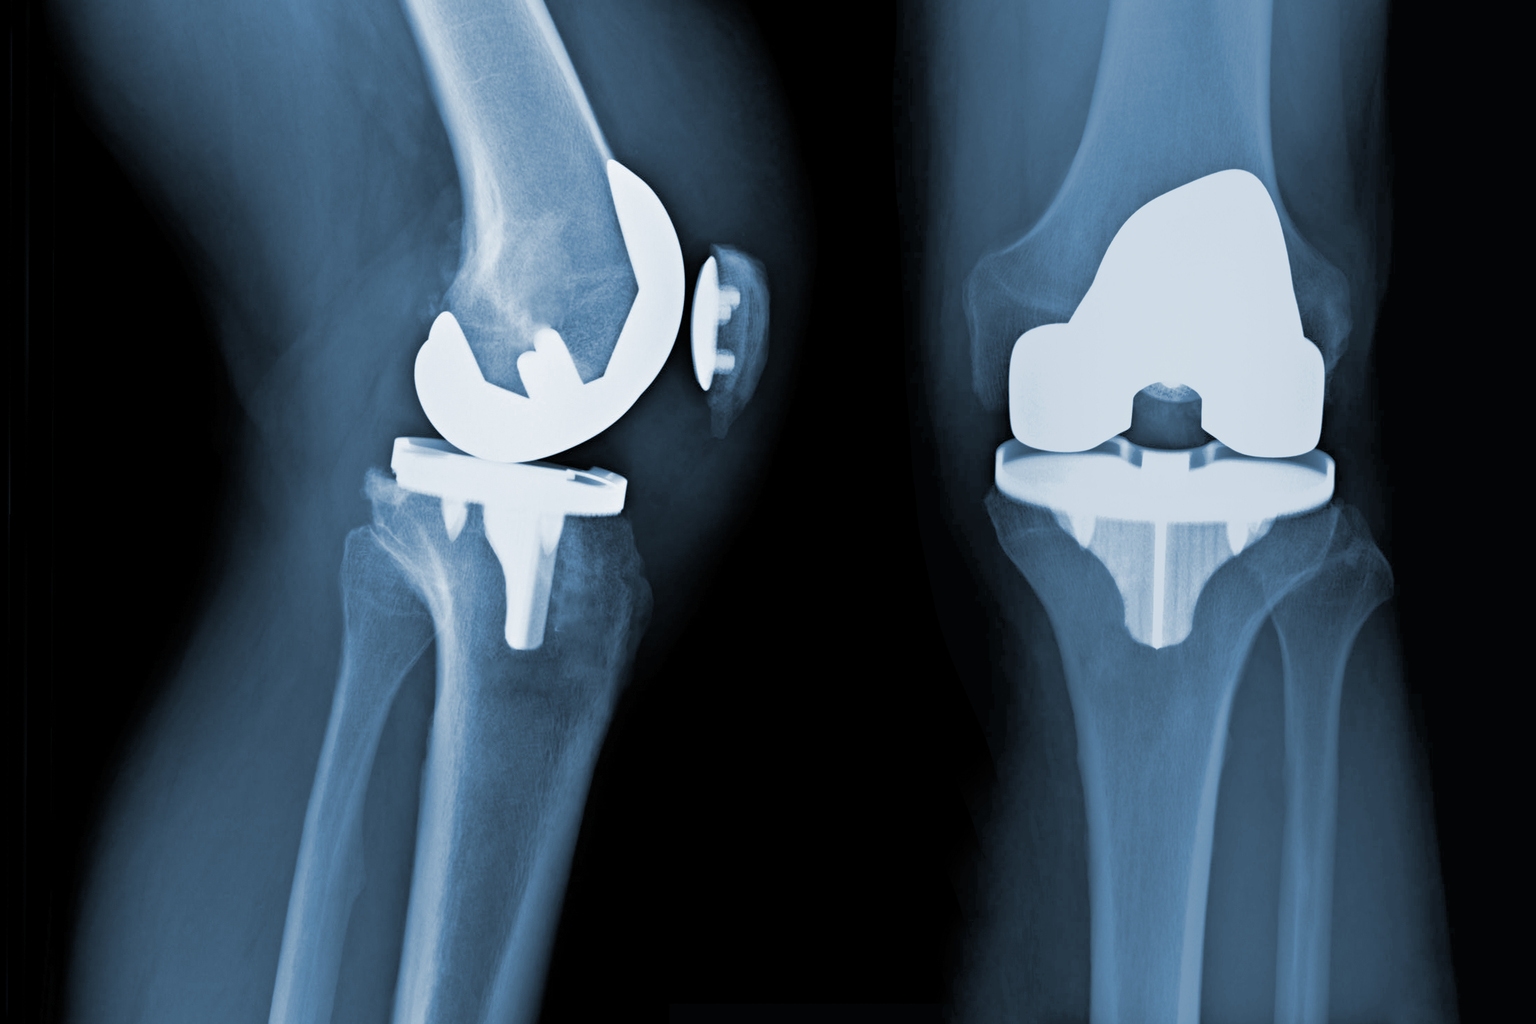

Core Insights - The 24th Chinese Orthopaedic Association (COA) conference showcased significant advancements in orthopedic technology, emphasizing the integration of robotics, navigation, imaging, and biomaterials under the theme "Digital Intelligence in Orthopedics" [2] - The conference attracted 20,188 registered participants and received 37,222 submissions, indicating a strong interest in orthopedic innovations [2] Group 1: Robotics and Navigation Systems - Surgical robots and navigation systems are expanding across various orthopedic fields, moving beyond joint surgeries to include spine, trauma, and sports medicine, focusing on precision and standardization [4] - Companies like Stryker, Tianzhihang, and others are presenting comprehensive orthopedic platforms that integrate imaging, navigation, and robotic arms, forming a closed-loop system for enhanced surgical outcomes [4] - The Trinity system by Tuo Dao Medical demonstrates a unified platform for rapid switching between surgical procedures, showcasing advancements in AI planning and real-time navigation [19] Group 2: Biomaterials and Bone Repair - The competition in bone repair and biomaterials is intensifying, with companies offering innovative solutions such as absorbable screws and 3D-printed bioceramics, focusing on osteogenic activity and infection resistance [4] - Smartbone and other manufacturers are introducing advanced materials that not only fill defects but also promote bone regeneration and integration [4] Group 3: Domestic Innovations - Domestic companies are accelerating the development of high-end joint prosthetics and key materials, with a focus on integrating materials, prosthetic design, and manufacturing processes [4] - The collaboration between local firms and international companies is shifting from product showcases to establishing standards and ecosystems, enhancing the overall orthopedic landscape [4] Group 4: Key Product Launches - Stryker highlighted its latest products, including the Mako robotic system, which integrates multiple surgical techniques for hip and knee replacements, enhancing precision and efficiency [5][7] - Rosenboht signed a strategic partnership with the Chinese University of Hong Kong to advance intelligent surgical technologies, aiming for more precise and minimally invasive orthopedic procedures [12][14] - The launch of the "Panshi Self-Pressing 3D Partition Bone Trabecular Biological Knee Prosthesis" by Jiashite Medical showcases advancements in mechanical stability and biological fixation [40][42] Group 5: Technological Integration - Companies are increasingly focusing on integrating AI and imaging technologies to enhance surgical precision and safety, as seen in the solutions presented by Meiya Optical and other firms [46][50] - The introduction of AR navigation systems by Linyan Medical represents a significant technological advancement, improving the visibility and accuracy of spinal surgeries [53][55] Group 6: Comprehensive Solutions - The conference highlighted the importance of comprehensive solutions that encompass preoperative planning, intraoperative guidance, and postoperative evaluation, as demonstrated by various exhibitors [4][60] - Companies like Weigao and others are showcasing integrated solutions that leverage digital technologies to enhance the entire orthopedic treatment process [100][102]